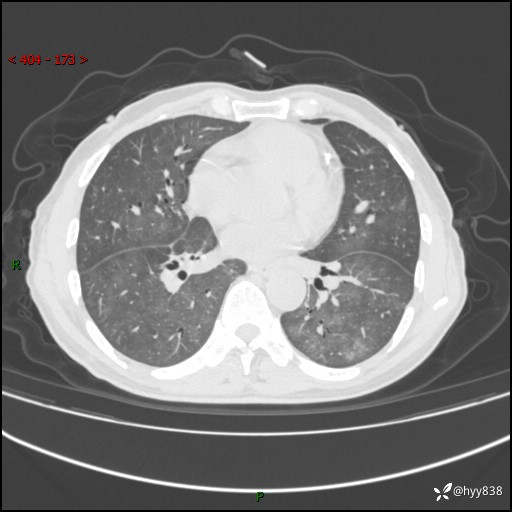

肺结节入院,CT却发现肺部弥漫性病变,what happened---(有结果)

主诉:检查发现左上肺结节4天

简要病史:患者于2024-01-15当地市人民医院胸部CT提示:左肺上叶(69)结节,最大截面约1.0 x 1.2cm,肿瘤病变待排。现患者活动后呼吸困难,自述平地行走200m后胸闷气喘,不伴咳嗽咳痰、头晕、恶心、呕吐等不适,未行特殊处理。现患者为求进一步治疗,于我院就诊,门诊拟“左上肺结节”收入院。 自患病以来患者食欲差,精神、睡眠尚可,大小便正常,体重近1月来下降5kg左右,体力明显减轻。

辅助检查:CT

胸部CT平扫

不是讨论肺部结节